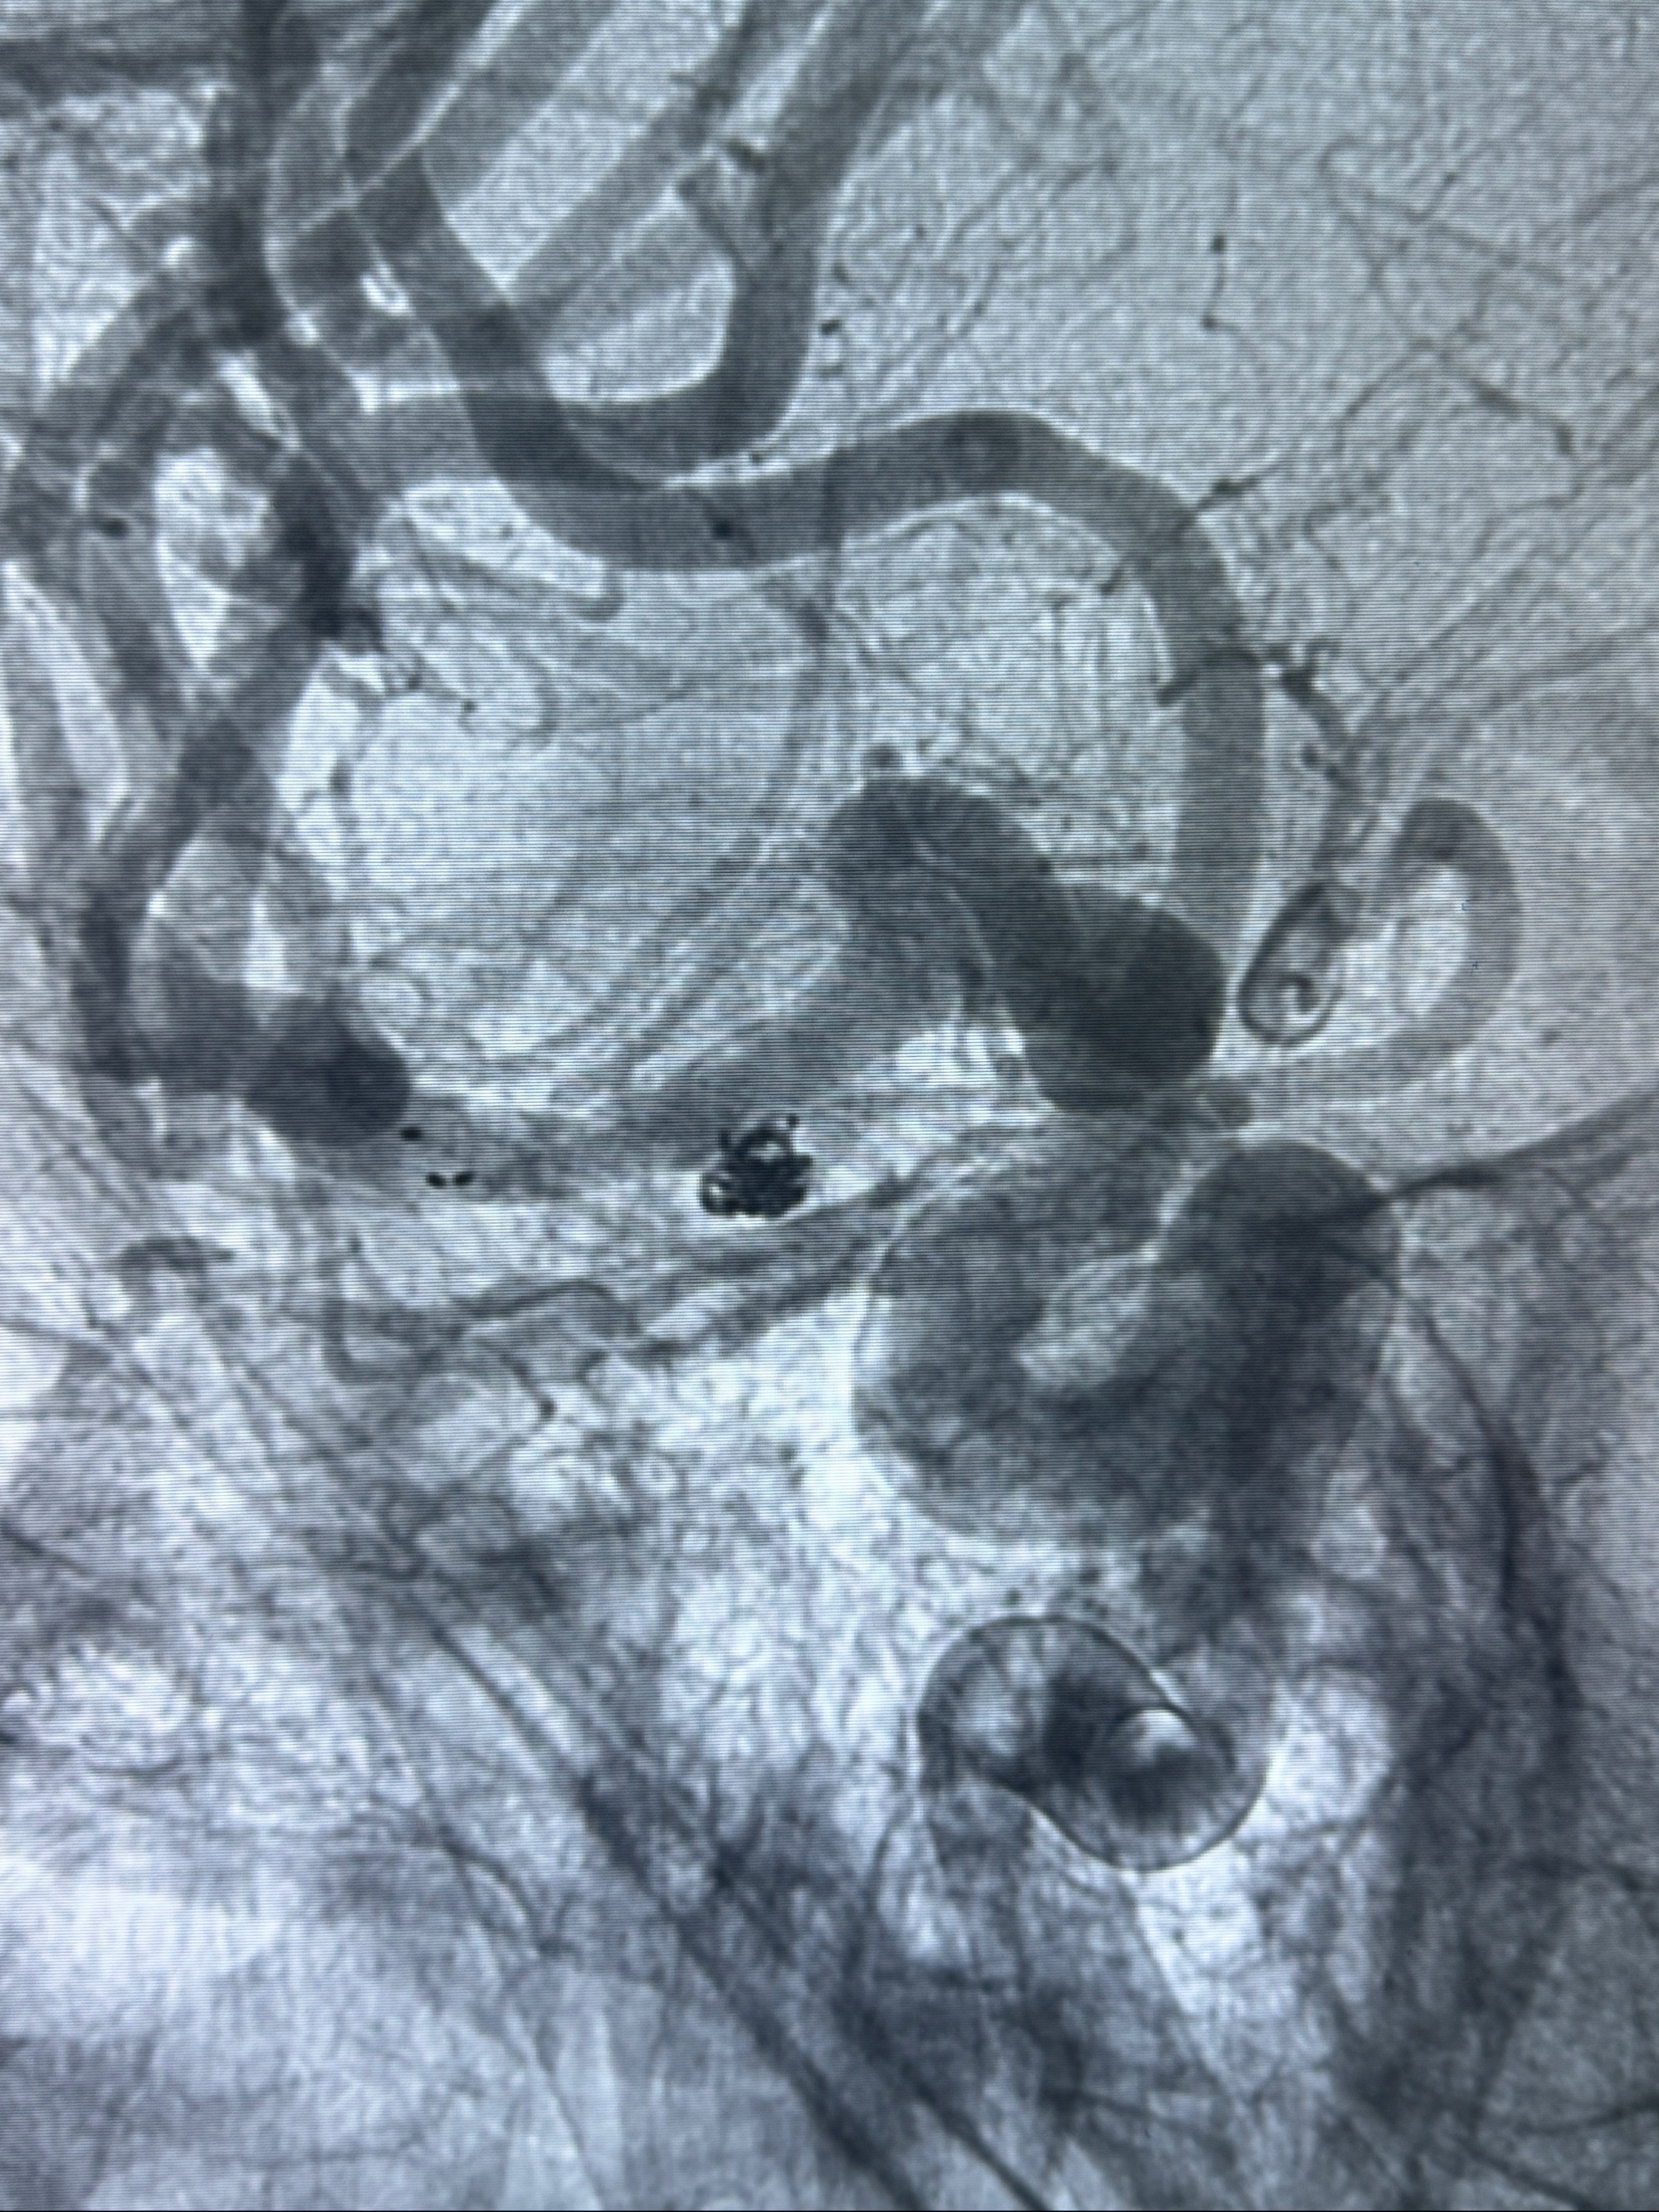

2023-12-04全麻下行支架辅助治疗

S-AB4-20mm

麻醉苏醒佳,遵嘱动作